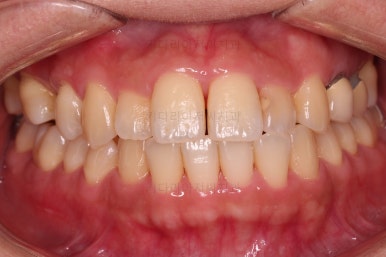

부산연산동치과 전후 사진을 비교해 보겠습니다.

총 22개월 걸렸고, 임플란트는 1개로 마무리를 했습니다.

처음에 충분히 다양한 치료옵션을 제시해 드렸었고, 입을 넣느냐/마느냐 임플란트를 안하느냐/1개를 하느냐, 기간이 많이 걸리느냐/적게 걸리느냐 등 다양한 관점에서 가장 합리적이다라고 판단되는 옵션을 선택하시어 그에 부합하는 치료로 마무리가 되었습니다.